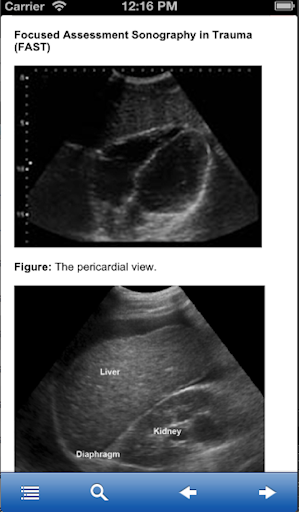

Focused Assessment Sonography Trauma

Please review the screen images before downloading.